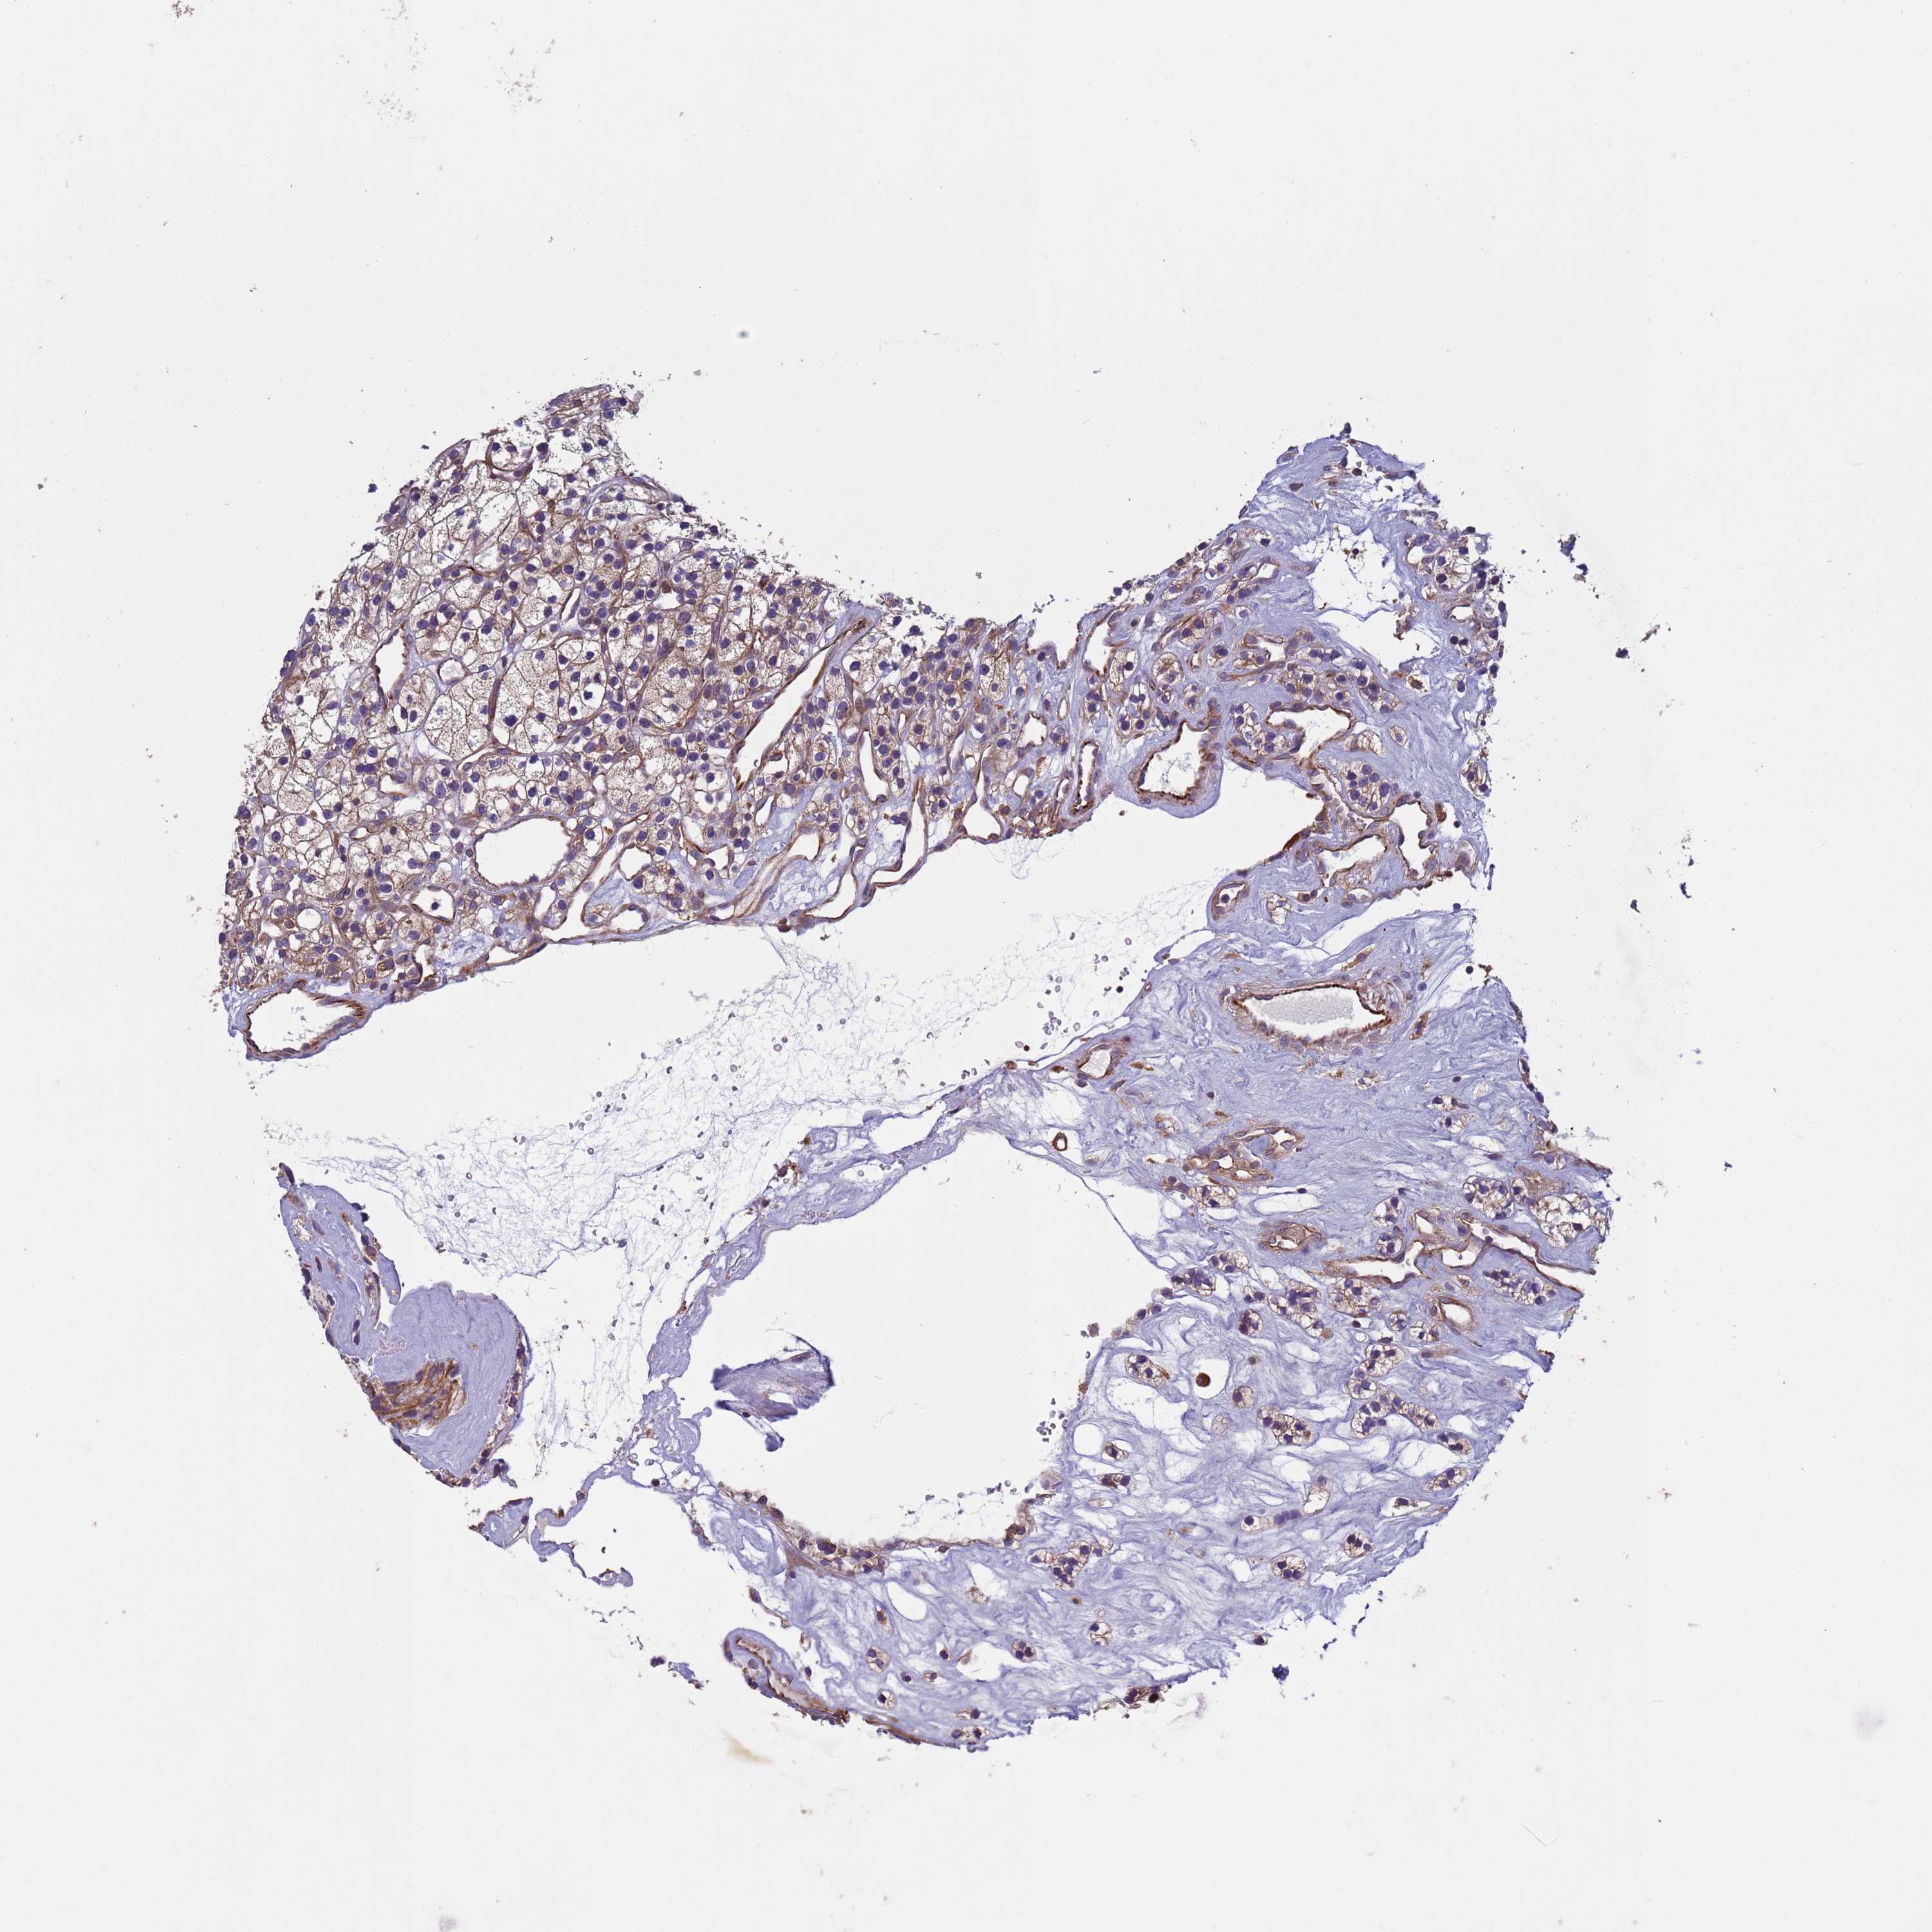

KIDNEY RENAL PAPILLARY CELL CARCINOMA (TCGA) - Interactive survival scatter ploti

The Survival Scatter plot shows the clinical status (i.e. dead or alive) for all individuals in the patient cohort, based on the same data that underlies the corresponding Kaplan-Meier plots. Patients that are alive at last time for follow-up are shown in blue and patients who have died during the study are shown in red.

The x-axis shows the expression levels (FPKM) of the investigated gene in the tumor tissue at the time of diagnosis. The y-axis shows the follow-up time after diagnosis (years). Both axes are complimented with kernel density curves demonstrating the data density over the axes. The top density plot shows the expression levels (FPKM) distribution among dead (red) and alive patients (blue). The right density plot shows the data density of the survived years of dead patients with high and low expression levels respectively, stratified using the cutoff indicated by the vertical dashed line through the Survival Scatter plot. This cutoff is automatically defined based on the FPKM cutoff that minimizes the p-score. The cutoff can be changed by dragging the vertical line or by entering a cutoff value in the square labeled "Current cut-off".

Under the Survival Scatter plot the p-score landscape (black curve; left axis) is shown together with dead median separation (red curve; right axis). Dead median separation is the difference in median mRNA expression between patients who have died with high and low expression, respectively. It is calculated as follows: median FPKM expression of dead patients with high expression - median FPKM expression of dead patients with low expression. This is intended to aid the user in visually exploring custom cutoffs and the associated p-scores and dead median separation.

Individual patient data is displayed and can be filtered by clicking on one or more of the category buttons on the top of the page. Categories describing expression level and patient information include: high, low, alive, dead, female, male and tumor stages. The scale of the x-axis can be toggled between linear and log-scale by clicking on the "x log" button. Mouse-over function shows TCGA ID, patient information and mRNA expression (FPKM) for each patient.

& Survival analysisi

Kaplan-Meier plots summarize results from analysis of correlation between mRNA expression level and patient survival. Patients were divided based on level of expression into one of the two groups "low" (under cut off) or "high" (over cut off). X-axis shows time for survival (years) and y-axis shows the probability of survival, where 1.0 corresponds to 100 percent.

RAB10 is potential prognostic, high expression is unfavorable in Kidney Renal Papillary Cell Carcinoma (TCGA)